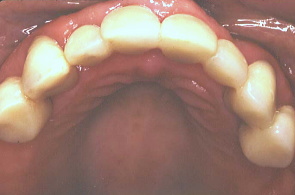

最初の写真は先にワックスで作った形を模倣して口腔内で再現し、仮り歯を作ったもの。次の写真は歯周外科を施し、深い歯周ポケットの歯垢を除去したところ。歯肉の色や艶が健康色を取り戻した。

口元と上の歯の仮り歯を拡大して撮影したところ。奥のほうの歯は義歯を入れる予定。